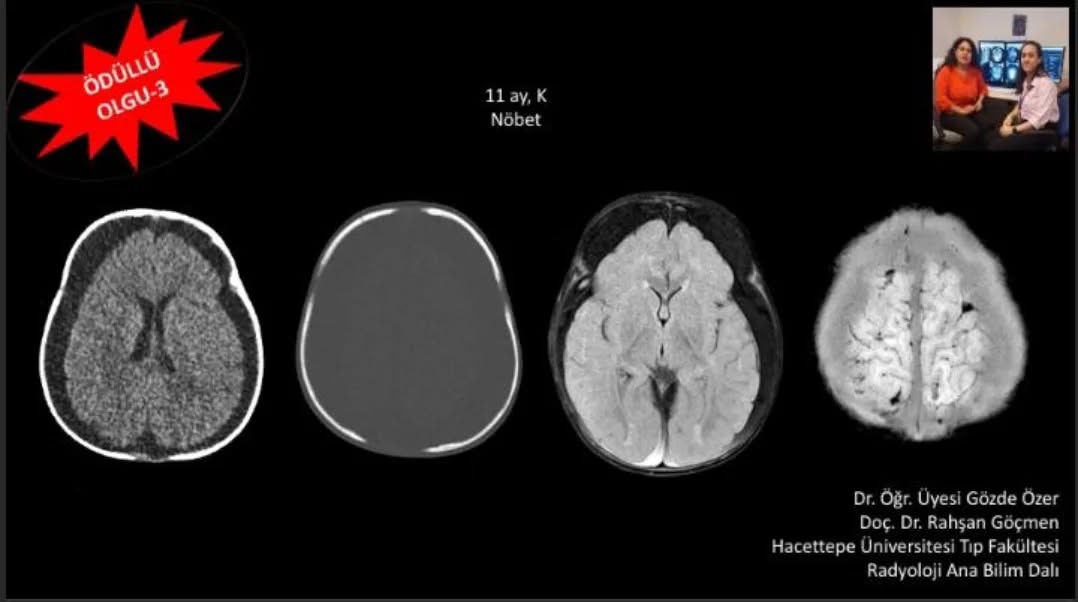

📣📣📣Haftanın ödüllü olgu sorusu yayınlandı.

Yanıtlarınızı www.tnrd.org.tr adresinden bekliyoruz.